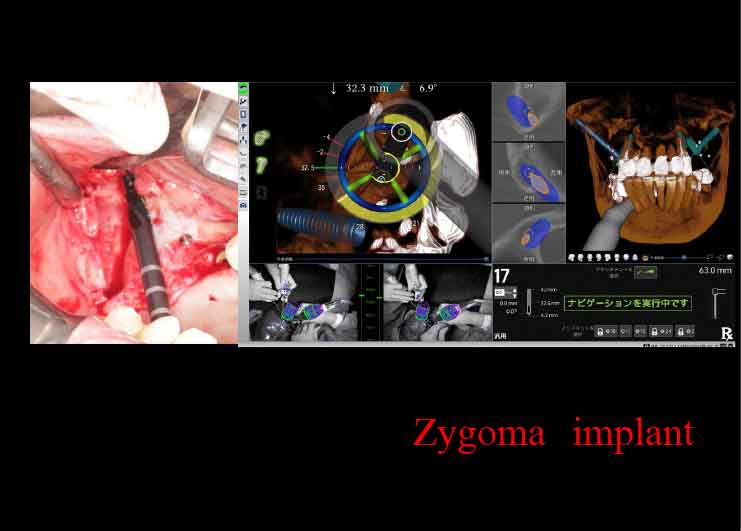

ザイゴマインプラント

上あごの骨が十分にない場合には、強固な頬骨に長めのインプラントを埋め込むことで、しっかりとインプラントを固定することができます。

X-ガイドにより、正確な手術が可能です。

X-ガイドにより、正確な手術が可能です。